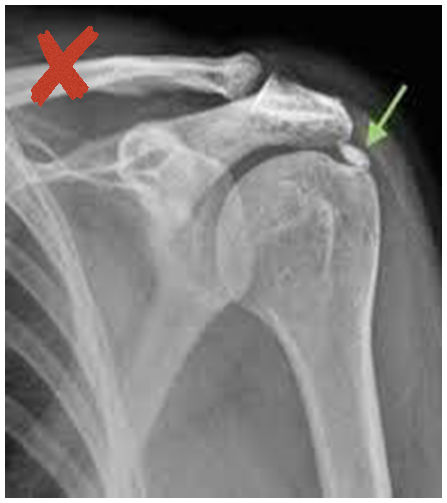

Ακτινολογική ταξινόμηση της ασβεστοποίησης στον ώμο (Gartner and Hayer)

Ανάλογα με την απεικόνιση στην ακτινογραφία ταξινομείτε ως εξής:

| Τύπος Ι : Ομαλά όρια, αυξημένη πυκνότητα ασβέστωσης. Φάση σχηματισμού | Τύπος ΙΙ: Σχήμα ομαλό, πυκνό ή οξύ, περιοχές ακτινοδιαπερατές. Φάση σταθεροποποίησης | Τύπος ΙΙΙ: Διάφανη, νεφελώδης εμφάνιση, χωρίς σαφή όρια. Φάση απορρόφησης |